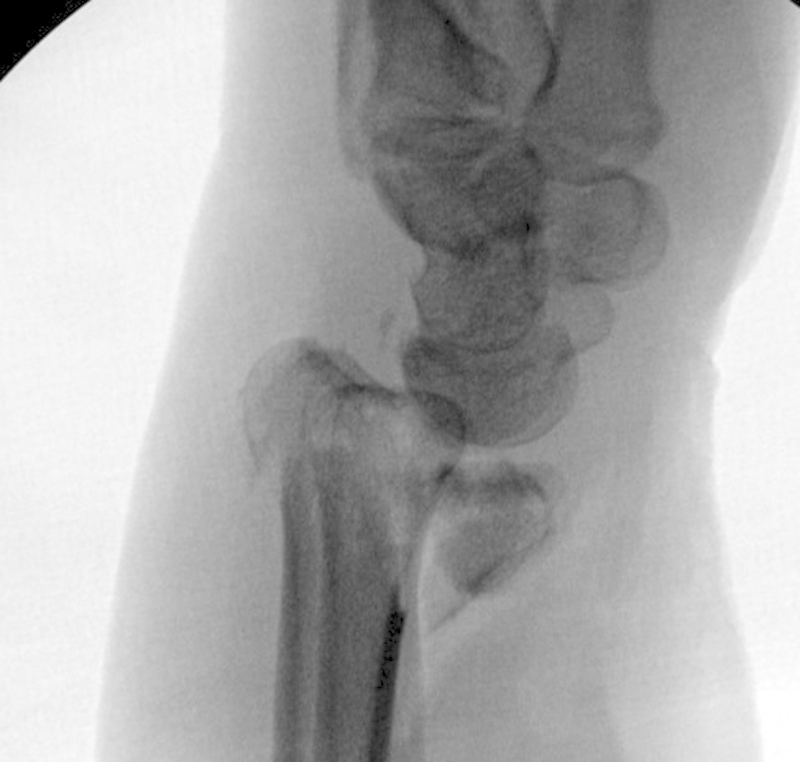

Fig. 6.

PA radiograph of a distal intra-articular fracture of the distal radius.

Fig. 7.

Lateral radiograph showing the distal intra-articular fracture of the distal radius.